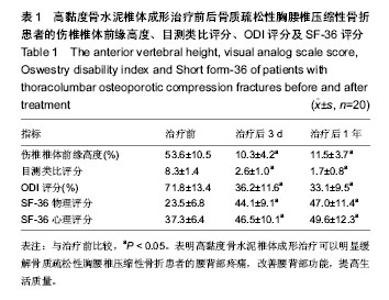

2.1 参与者数量分析 20例患者均顺利完成手术,完成1年以上随访,按意向性处理分析,20例均进入结果分析。 2.2 伤椎椎体前缘高度恢复 治疗后患者伤椎椎体前缘高度得到明显改善,由治疗前的(53.6±10.5)%到治疗后 3 d的(10.3±4.2)%和治疗后1年的(11.5±3.7)%,治疗前后椎体高度比较差异有显著性意义(P < 0.05),治疗后3 d和治疗后1年椎体高度比较差异无显著性意义(P > 0.05),见表1。 2.3 腰背部疼痛及功能恢复情况 术后腰背部疼痛明显缓解或消失,腰背部功能明显改善,生活质量评分得到明显提高,治疗后3 d及1年的目测类比评分、ODI评分明显低于治疗前(P < 0.05),治疗后3 d和治疗后1年的目测类比评分、ODI评分比较差异无显著性意义(P > 0.05)。治疗后3 d及1年的SF-36物理评分及心理评分均高于术前(P < 0.05),治疗后3 d和治疗后1年的SF-36物理评分及心理评分比较差异无显著性意义(P > 0.05),见表1。治疗后神经功能均正常为Frankle E级,与治疗前相同。 2.4 并发症及不良反应 所有手术均顺利完成,每个椎体注射骨水泥量2-5 mL,术中血压及血氧饱和度均正常。治疗后随访12-18个月,平均14.5个月。术后复查X射线及CT见骨水泥弥散良好,只有1例发生椎管内少量骨水泥渗漏及1例椎体前方渗漏,但无任何临床症状,无骨水泥毒性或过敏反应、肺栓塞、感染和神经损伤等并发症发生。随访期间无新发骨折。"